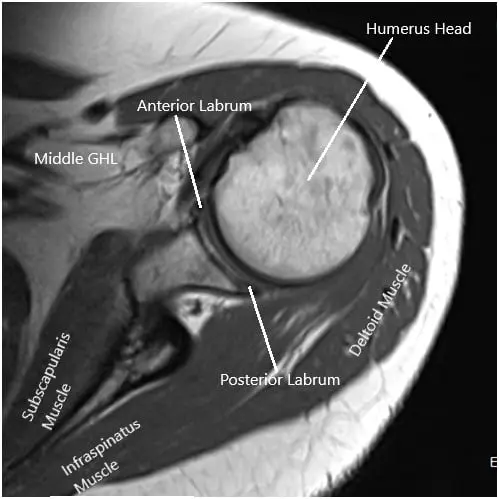

La resonancia magnética del hombro izquierdo sugirió tendinosis del tendón supraespinoso con una ruptura parcial de la superficie articular de las fibras anteriores y medias del tendón. Tendinosis del tendón infraespinoso. Líquido bursal subacromial/subdeltoideo que refleja bursitis. Degeneración y desgarro del labrum anterosuperior.

Imagen por resonancia magnética del hombro en secciones axial y coronal